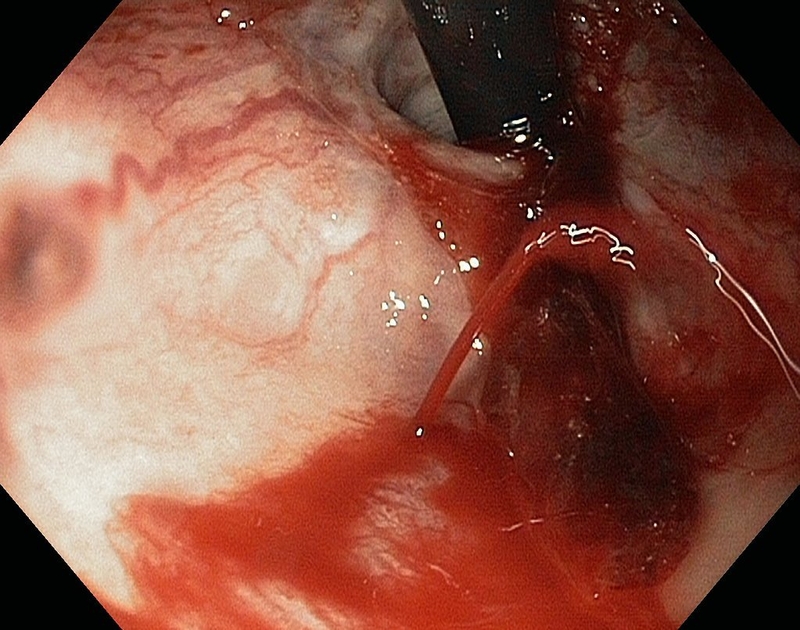

Đây là phương pháp dùng một ống soi mềm có gắn camera và đèn chiếu sáng ở đầu để đi qua họng và đi dọc theo chiều dài của thực quản. Dụng cụ nội soi này có đường kính nhỏ, có thể điều khiển được hướng đi và góc nhìn nên có thể quan sát, phát hiện ra những tổn thương dù là rất nhỏ của thực quản và có khả năng can thiệp ngay khi cần.

Mục đích chính của việc nội soi thực quản là phát hiện các bất thường ở lớp lót của thực quản. Những bất thường chủ yếu khi nội soi ra là:

• Viêm loét thực quản.

• Ống thực quản bị chảy máu trong.

• Có xuất hiện polyp hoặc có sự bất thường tại thực quản.

Tiếp đến, người bệnh sẽ nằm nghiêng và quay về bên trái. Bác sĩ sẽ truyền thuốc an thần. Khi thuốc có hiệu lực, sẽ tiến hành đưa ống nội soi qua miệng vào thực quản, dạ dày và tá tràng. Lúc này, nhờ có camera và đèn chiếu sáng mà bác sĩ có thể thấy được ống thực quản, niêm mạc thực quản của bệnh nhân. Trong quá trình nội soi, bác sĩ có thể dùng ống nội soi để lấy một số tế bào hay mô có sự bất thường để sinh thiết.